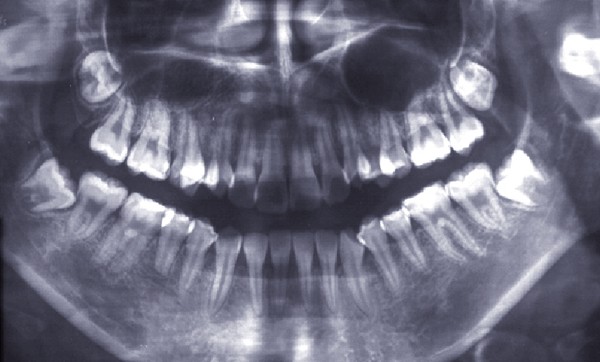

Diagnostic (fig. 1 à 3)

Sylvie se présente à l’âge de 15 ans avec une classe III squelettique (ANB -7,6°) d’origine maxillaire et mandibulaire sur un schéma facial à tendance hyperdivergent (FMA 31°) (fig. 1).

La classe III d’Angle et l’occlusion inversée s’accompagnent de signes de compensations alvéolo-dentaires : vestibuloversion des incisives supérieures (I/SN 114°) et linguoversion des incisives inférieures (IMPA 86°). L’encombrement à l’arcade maxillaire est important, souligné par des canines en infra-mésio-vestibulo-position.